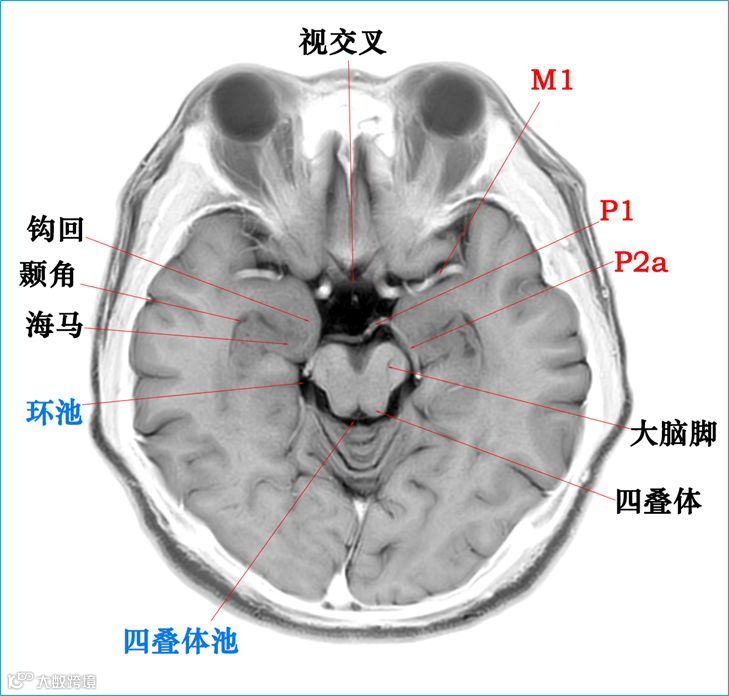

在T2WI反相图学下的颅脑断层解剖(吴晓安老师亲自手动标准)以及标本断层解剖,满满干货,坐在小板凳上,一起学习吧……